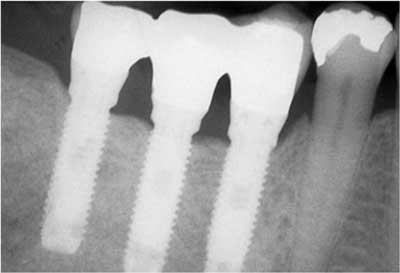

La incorporación de la implantología en la práctica odontológica ha representado un gran avance para la rehabilitación-restauración de la perdida de los dientes. Antes se instalaban prótesis apoyadas en otros dientes o sobre la mucosa bucal produciéndose todo tipo de complicaciones. Los implantes dentarios son fijaciones (tornillos) de titanio con superficies bioactivas que se colocan en los maxilares (intraóseos), imitando una raíz dentaria aunque su comportamiento es diferente.

Las fijaciones o implantes se pueden instalar en el hueso alveolar de forma inmediata (tras la extracción del diente) o de forma diferida (al cabo de unos meses cuando la mucosa y el hueso este cicatrizado). Igualmente la prótesis puede colocarse de forma inmediata (es una prótesis provisional y normalmente fuera de oclusión) o de forma diferida (cuando el implante esta osteointegrado: 2-4 meses en la mandíbula y de 4 a 6 meses en el maxilar superior).

Normalmente se prefieren colocar prótesis fijas sobre los implantes (atornilladas o cementadas) aunque también pueden indicarse prótesis removibles (de poner y quitar) pero que están apoyadas sobre los implantes y no sobre otros dientes o sobre la mucosa bucal y el hueso alveolar.